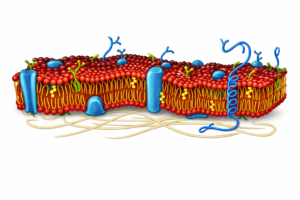

Essential phospholipids (EPLs) are purified extracts rich in phosphatidylcholine, a key structural component of cell membranes. As amphipathic molecules, phospholipids form the bilayer architecture essential for membrane integrity and function.

In hepatocytes, they maintain membrane fluidity, support enzyme function, mediate signaling, and regulate nutrient transport. Therapeutic EPLs – typically derived from soybeans, egg yolk, or sunflower seeds integrate into damaged liver cell membranes, aiding in repair and regeneration.

Phospholipid incorporation: EPLs integrate into the damaged hepatocyte membranes, restoring membrane fluidity, integrity, and function.

Membrane bound enzyme activity: Normalization of the function of enzymes embedded in hepatocyte membranes (e.g., ATPases) enhances cellular transport and metabolism.